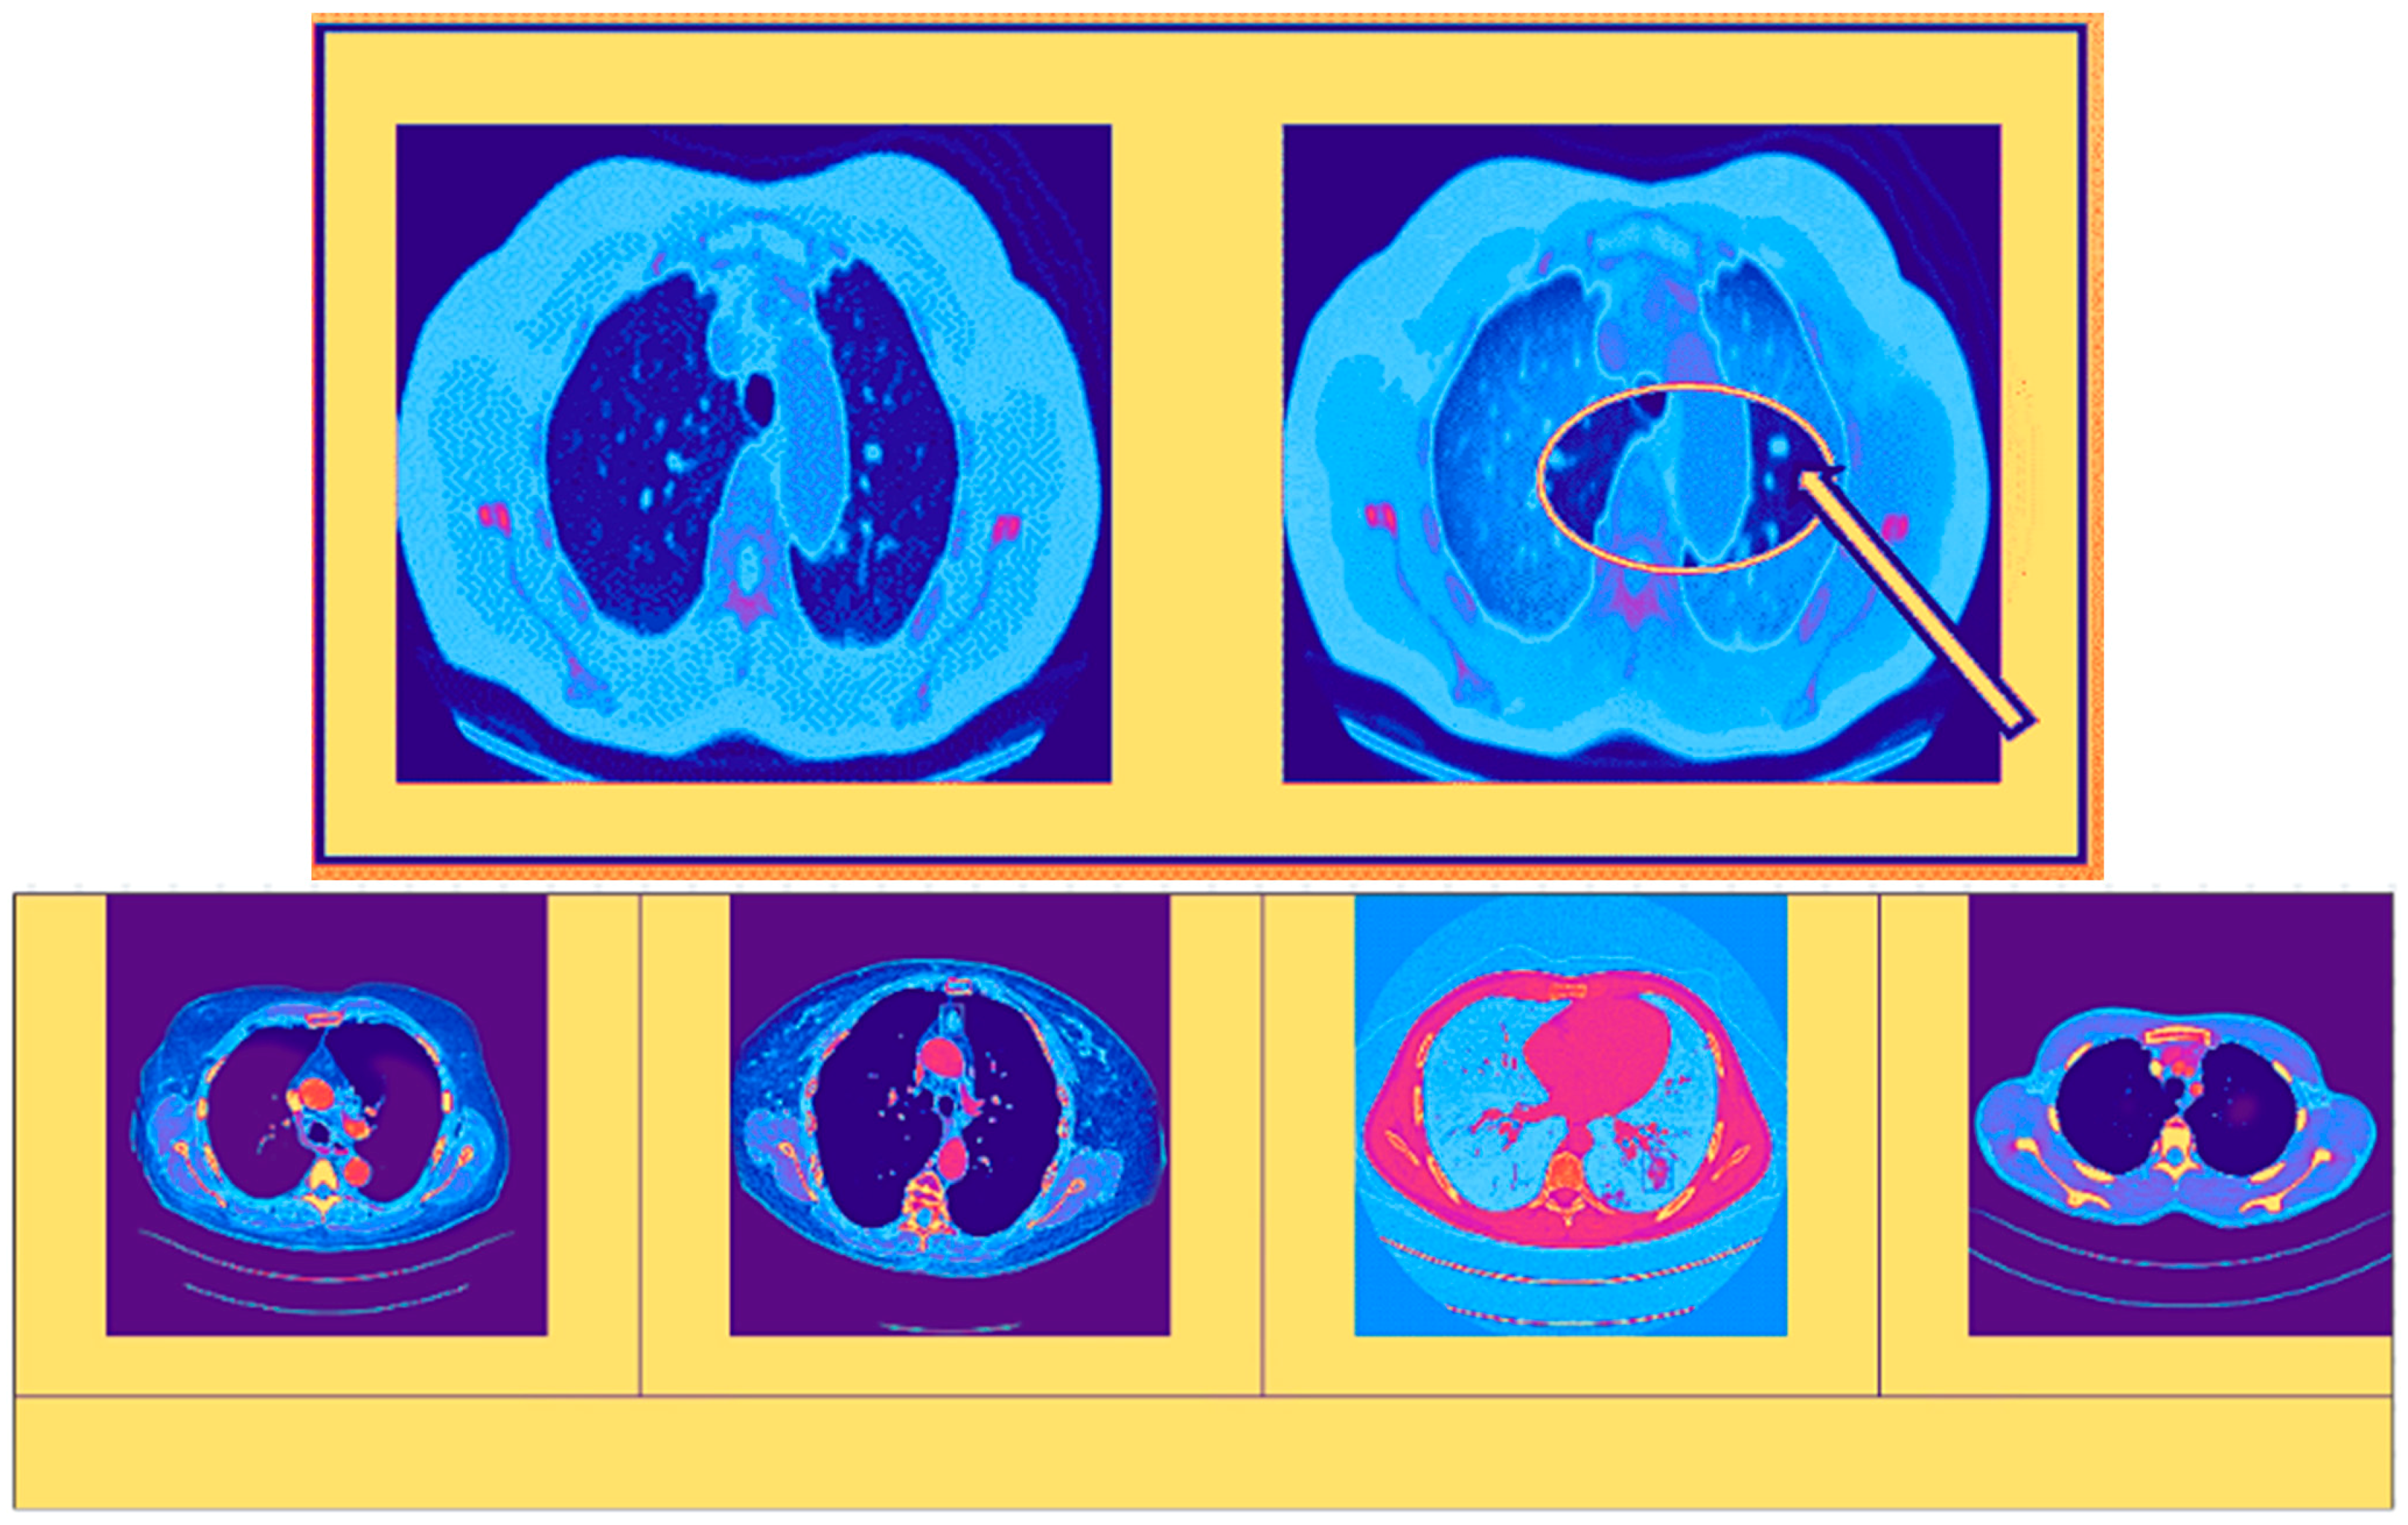

3.1. Processing Phase

3.2. Segmentation Phase

4. Results and Discussions